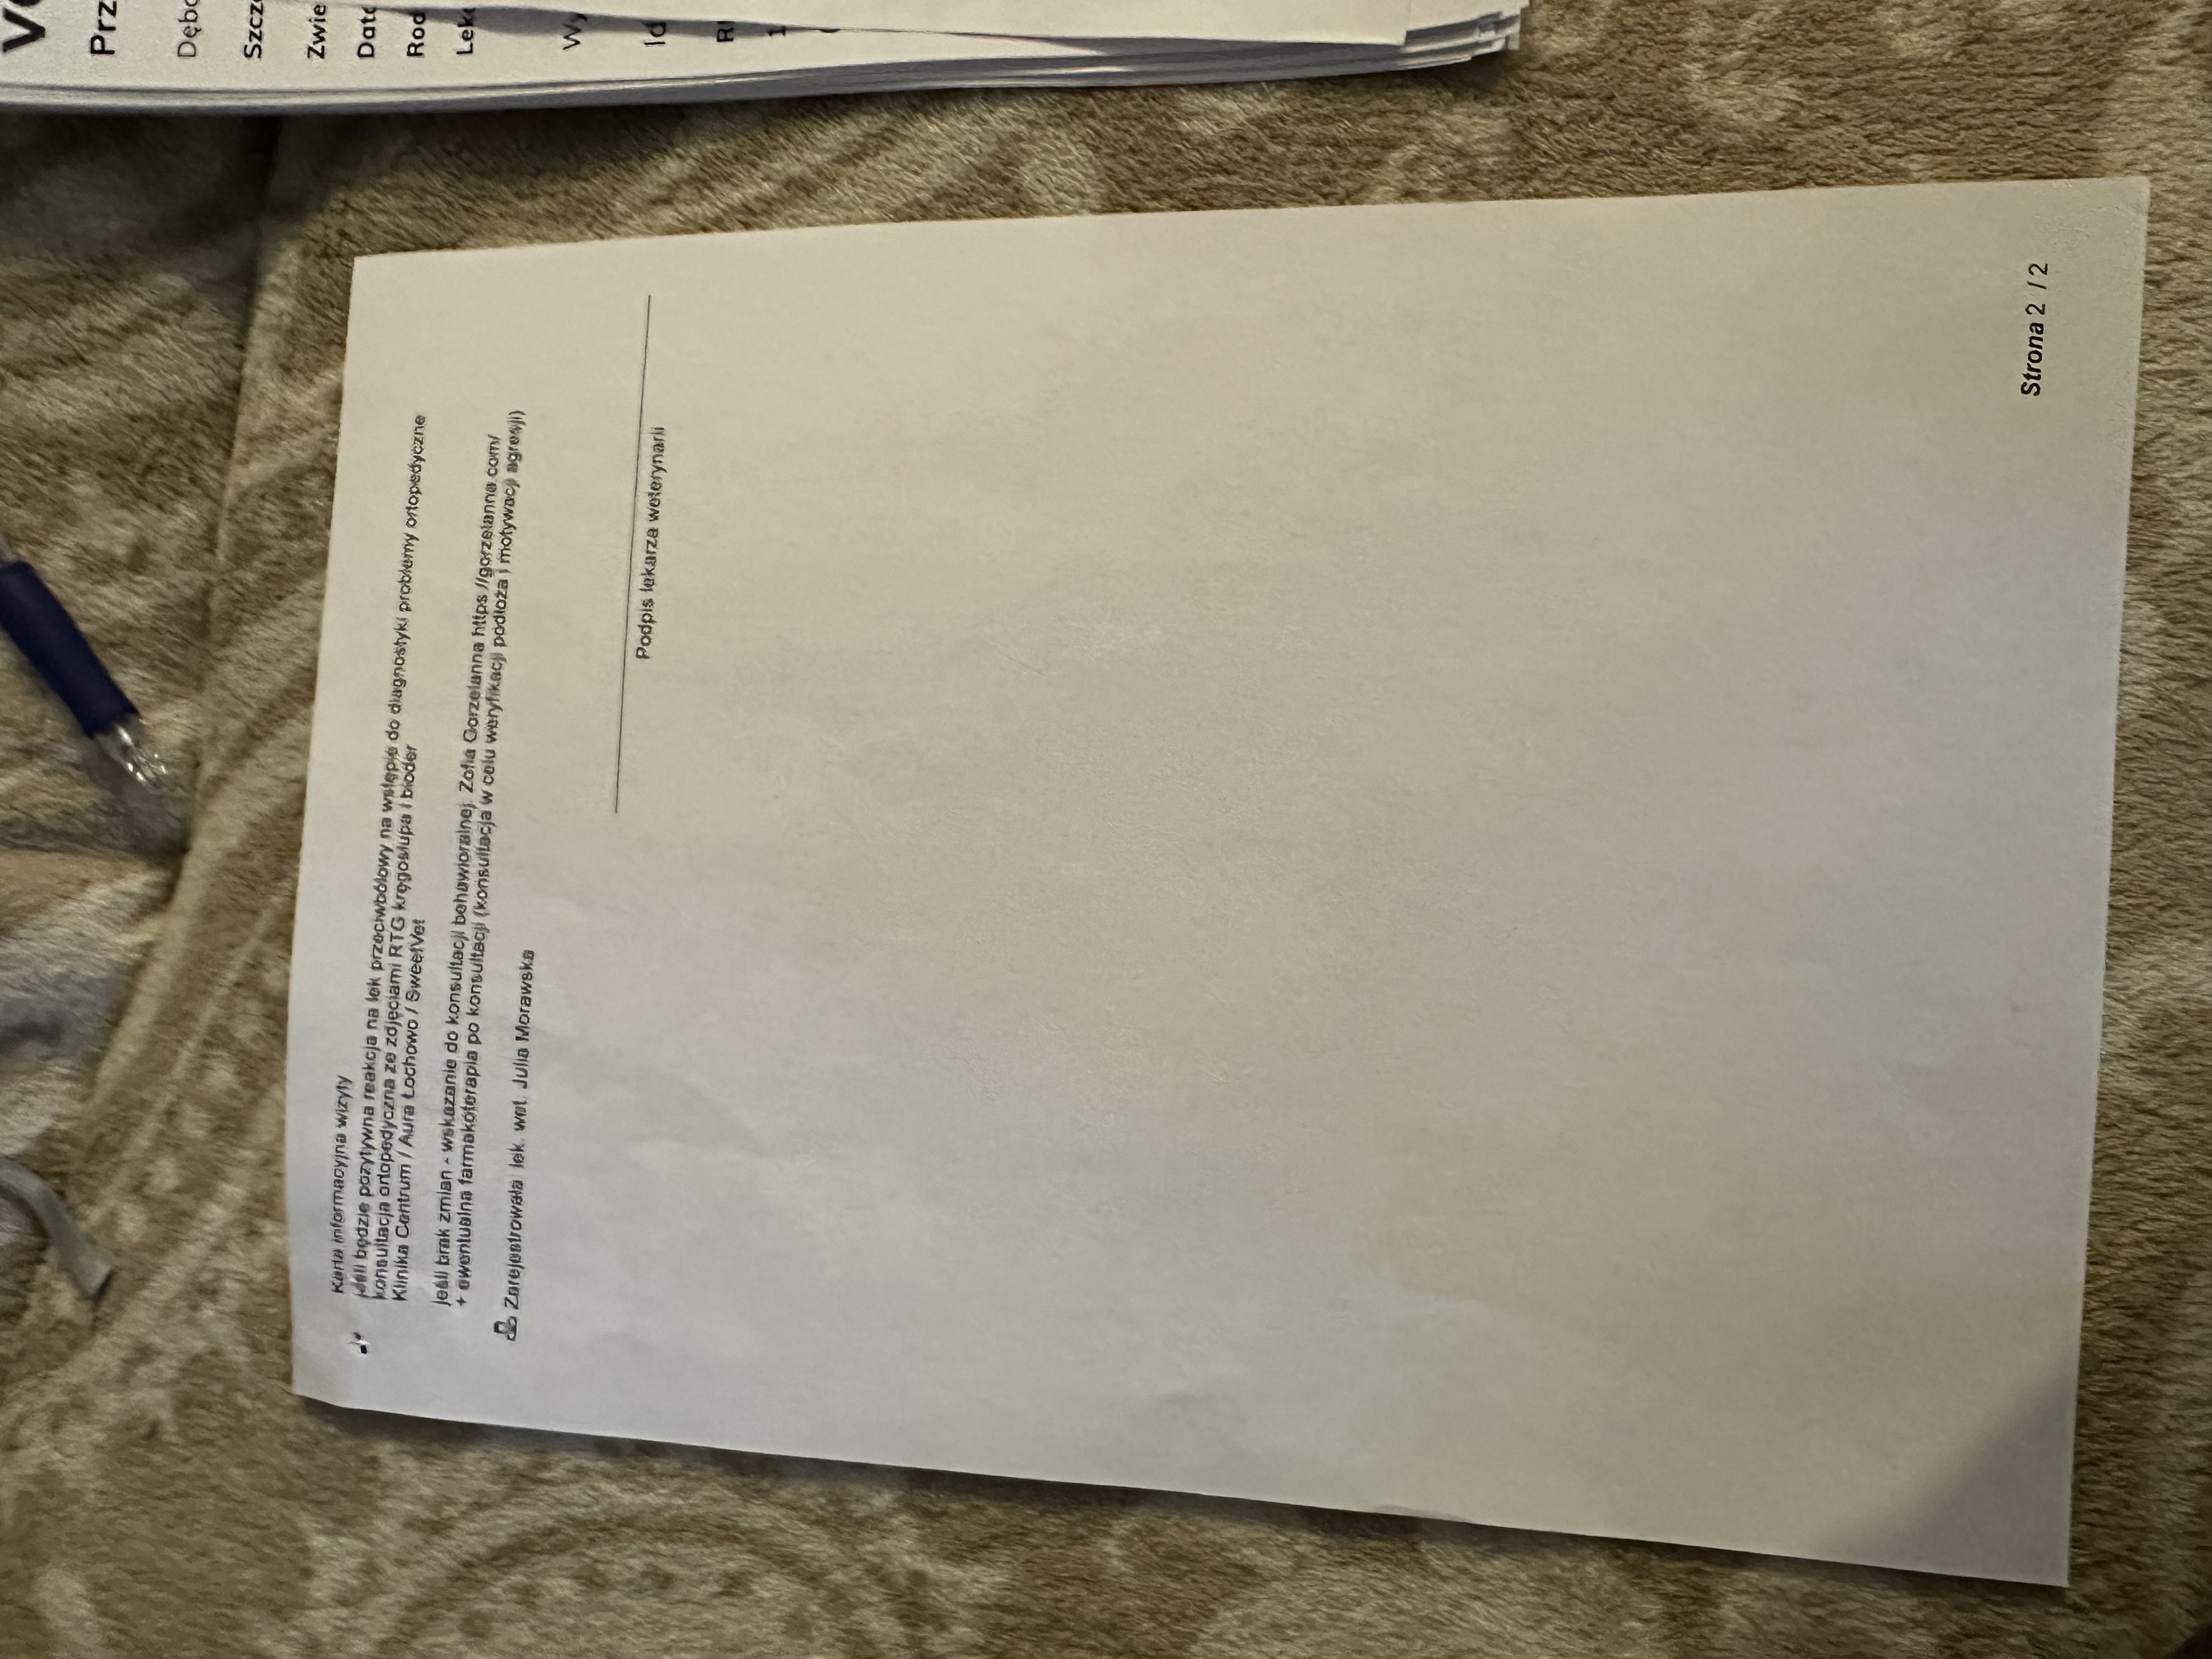

Kolejna konsultacja miała miejsce w innej klinice, gdzie lekarze nadal podejrzewali problemy ortopedyczne, dlatego przeszedł szczegółowe badania, w tym RTG kręgosłupa i bioder i konsultacje specjalistyczną. Wdrożono leczenie Gabapentyną oraz Metacamem, aby zmniejszyć ból i uspokoić kota. Zalecono dalszą obserwację oraz ewentualne kolejne badania, jeśli objawy nie ustąpią.

Kot wymagał dalszej diagnostyki – możliwe kolejne badania ortopedyczne (TK/MRI) oraz USG i biochemię z morfologią.